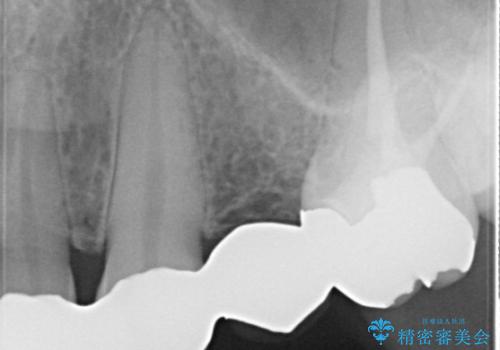

- 昔装着したかぶせ物が、不自然なのでやりかえたいとのことで来院されました。

また奥歯にまたがるブリッジも金属のもので、適合もよくありませんでした。

オールセラミックによるやりかえを行いました。